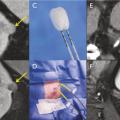

Cryothérapie sous anesthésie locale des tumeurs rénales

Publié le 20 Janvier 2018 || La Revue du Praticien || 68(1):45-7

L’incidence du cancer du rein localisé et de petite taille est en permanente augmentation depuis plusieurs décennies. Cela s’explique en partie par l’essor de l’imagerie médicale puisque plus des deux tiers des cancers du rein sont découverts fortuitement au cours d’un examen d’ima- gerie réalisé pour une autre raison.1, 2 Le…